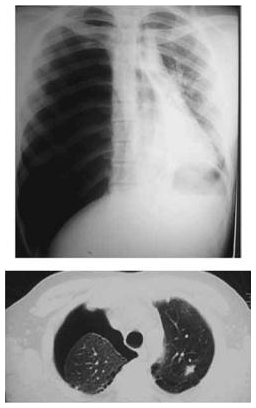

Paciente, portador de asma grave, durante um exame de tomografia de tórax sem contraste apresenta acesso de tosse, dispneia súbita e chiado intenso no peito. O exame físico revela o paciente taquidispneico, SO2 = 79%, PA = 90x50 mmHg e frequência cardíaca = 100 bpm. Ausculta pulmonar com sibilos expiratórios difusos à esquerda e murmúrio quase inaudível em hemitórax direito. A gasometria colhida na emergência mostra: pH = 7,28 / pCO2 = 52 / pO2 = 56 / HCO3 = 28 / SO2 = 78%. As imagens radiológicas estão ilustradas a seguir.